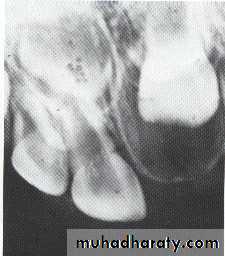

Radiolucency at apex of endodontically treated tooth

A: Radiolucent apical scar left after successful endodontic treatment..

B:New bone forming from the periphery of theLesion.

If the R.L.enlarged, pain,sinus,or no regression in the size of lesion after 6months (P. A. Cyst).

Apical scar